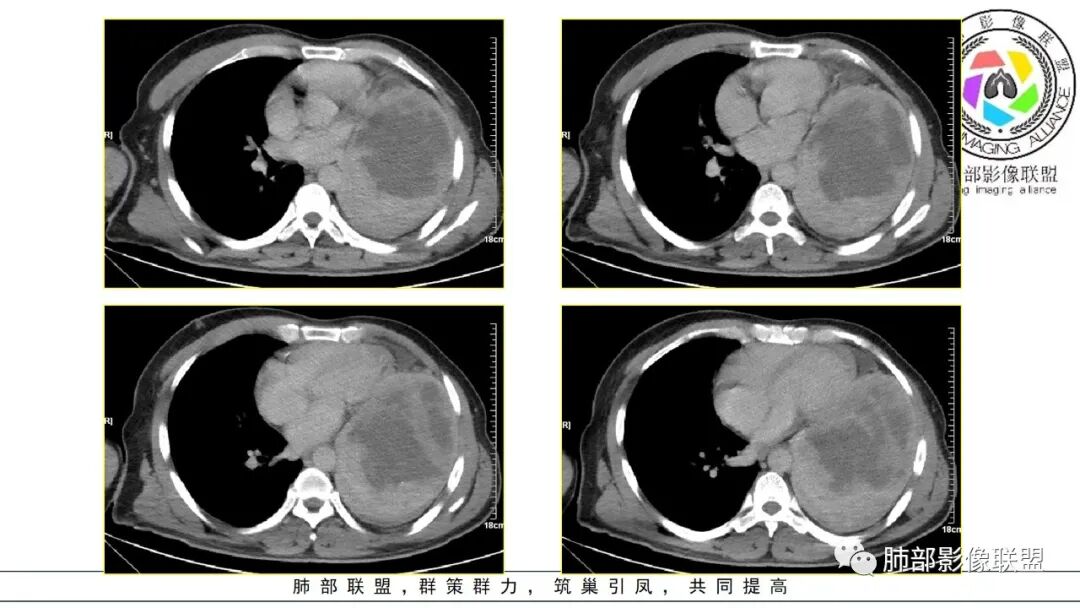

左下肺动脉分支进入肿块,考虑肺内病变。巨大肿块,不均匀强化,较多囊变坏死,少许钙化,考虑恶性肿瘤,以癌肉瘤、肉瘤样癌、肉瘤类、肺母可能

左侧巨大不规则肿块,密度不均,膈胸膜显示不清,增强后呈不均匀强化,内见片状坏死区,上叶支气管壁增厚,腔局部狭窄,肿块推挤心脏及血管向对侧偏移,考虑恶性,1胸膜来源,SFT。2下叶间叶组织来源肉瘤。

晨读:左肺下叶大肿块,自膈肌向上生长,边缘光滑,周围肺组织受压推移,平扫密度均匀,增强扫描不均匀强化,考虑恶性肉瘤(滑膜肉瘤,成人肺母细胞瘤),鉴别SFT

2.左肺巨大块影,上部边界较清楚,占据胸腔大部,对于左肺,“占据”及“推移”兼而有之,左肺上叶支气管推移狭窄,下叶支气管截断。下肺动脉穿行!

3.病灶密度不均,轻度强化,坏死或液化范围甚大,边界可分辨,部分“壁”可见钙化。

4.病灶紧贴胸壁,胸壁未见栽赃侵入。

5.纵隔左移,左肺门变形。左肺门及纵隔未见明显增大淋巴结。